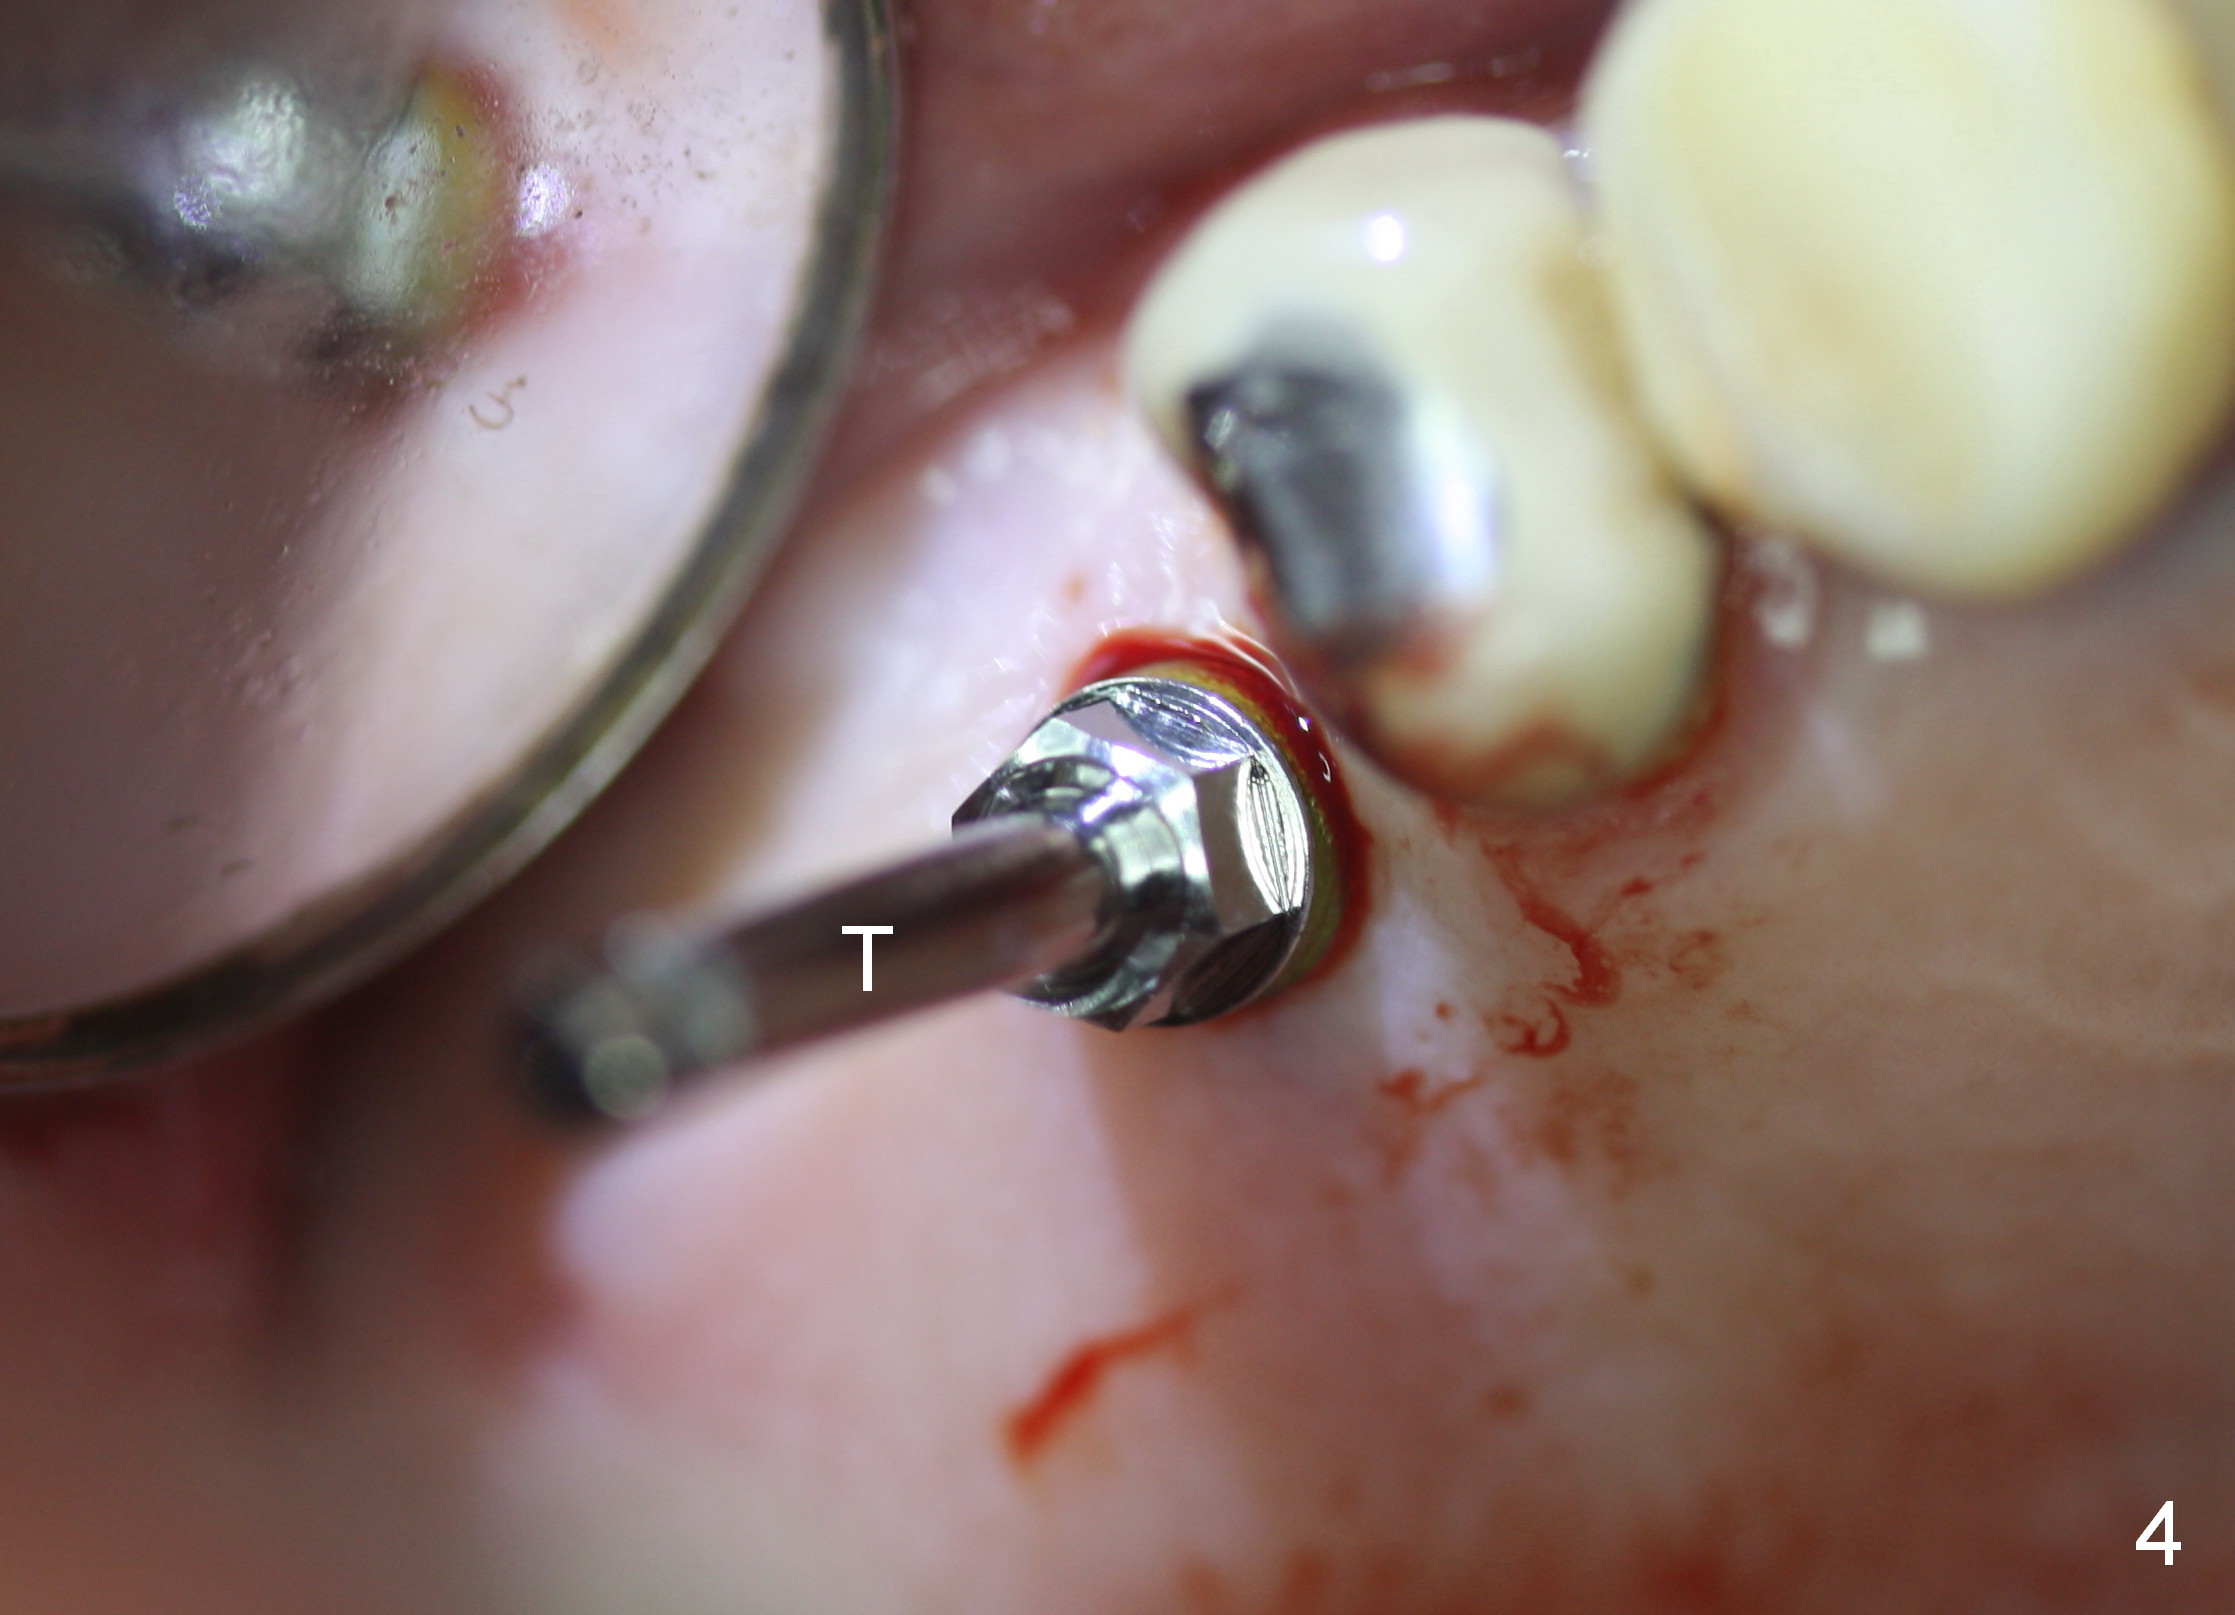

Both the teeth #30 and 31 are supraerupted. There is no restorative space for #2. So #3 implant will support the most distal crown. A 4 mm tissue punch is used, followed by a 2 mm pilot drill. Bone type is 3. A parallel pin shows that the trajectory needs to be adjusted (Fig.2). By the time a 4.5 mm tap is placed, the trajectory is within normal limit (Fig.3,4 T). A 5.3x10 mm implant is placed with insertion torque > 60 Ncm (Fig.5; *: sinus lift). After insertion of an abutment, an immediate provisional is fabricated with intention to prevent further supraeruption of the tooth #30 during #3 implant osteointegration.